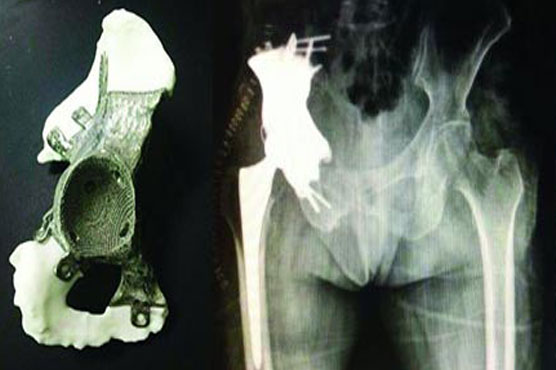

Summary Surgeons removed half the patient's pelvis with part of his hip replacing them with a prosthetic

In an 11.5-hour operation on Tuesday, surgeons removed half the patient s pelvis along with part of his hip affected by the cancer, replacing them with a prosthetic made in the United States from titanium covered in tantalum, a non-corrosive metal mainly used in electronics components.